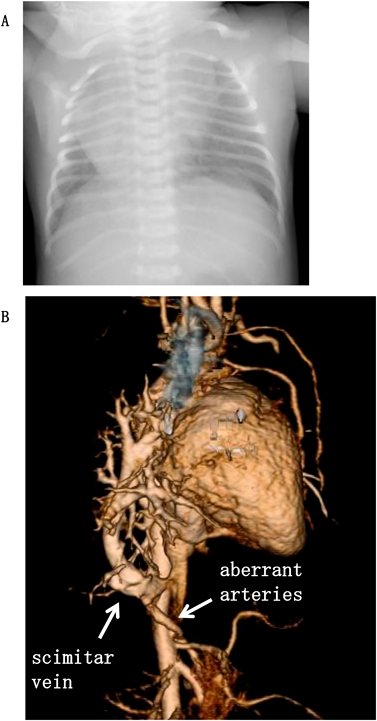

異なる生命予後を示したscimitar症候群の同胞例とリスク因子の検討Familial Scimitar Syndrome with Different Outcomes and Risk Factors